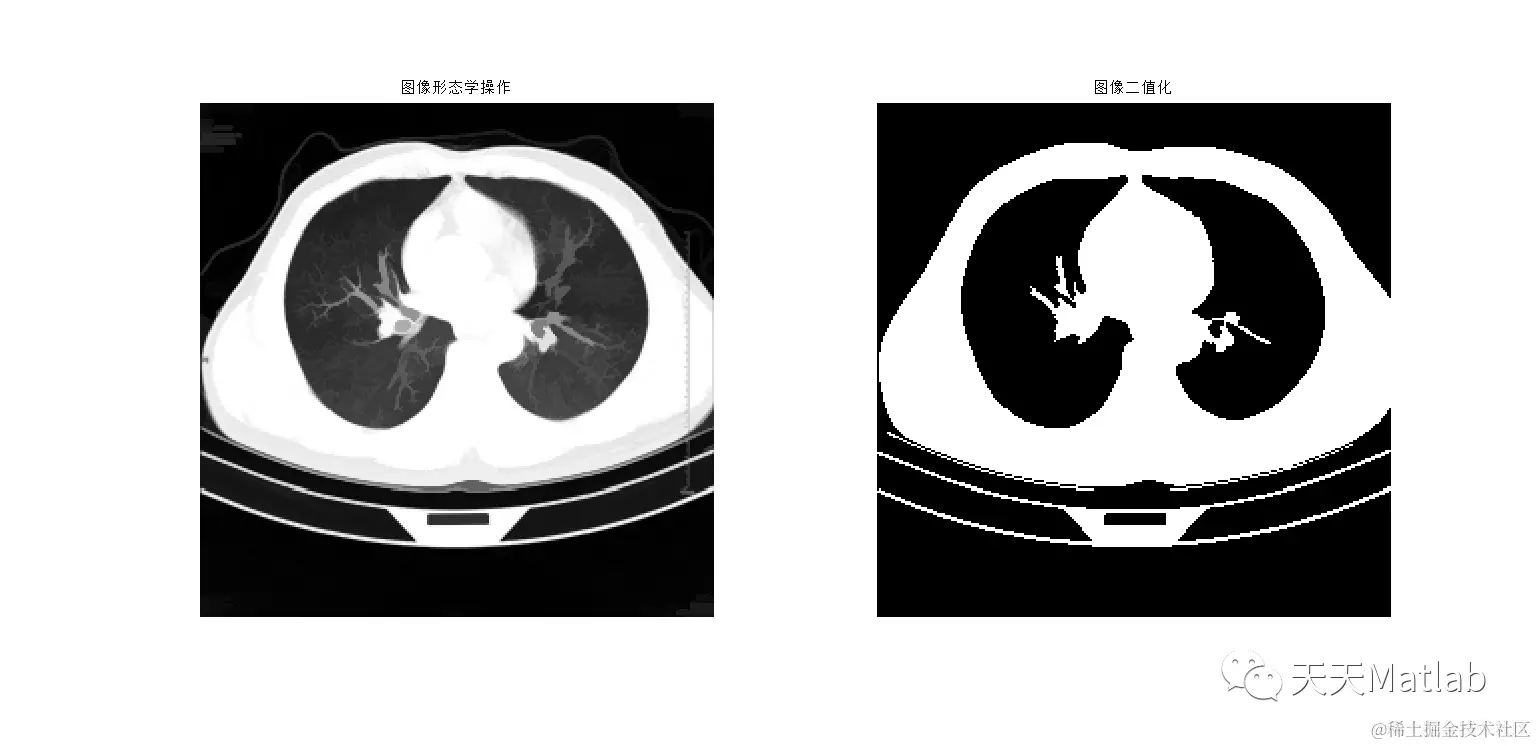

3 仿真结果